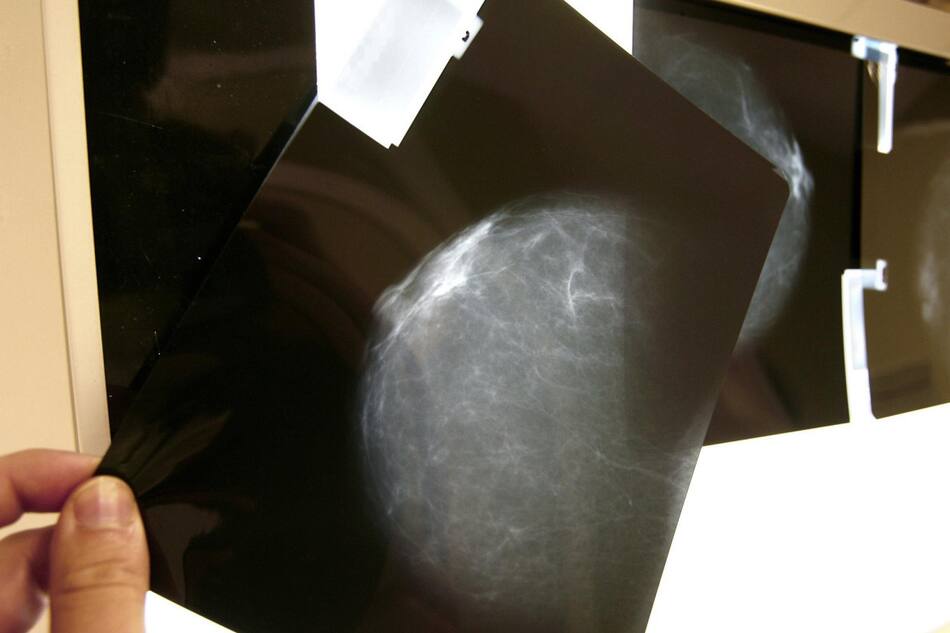

Rayos x de pecho, Salud. Foto: Unsplash